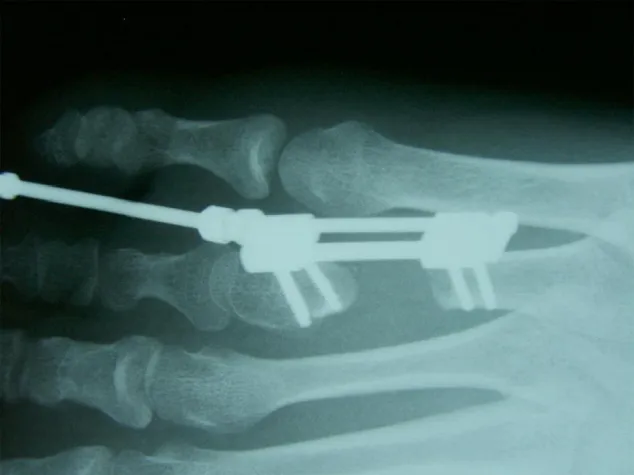

Röntgenbild eines kindlichen Fußes mit implantiertem Minifixateur interne zur Verlängerung der verkürzten Zehenstahlen

(openPR) Erstmals ist es gelungen an einem Fuß gleich zwei interne Fixateure zur Verlängerung von zu kurzen Zehen (3. und 4. Zehenstrahl) zu implantieren. Der Entwickler des sogenannten Minifixateur interne - Dr. H. Klauser, Leiter des Hand- und Fußzentrum Berlin - hat am 29. Juni 2009 in Hamburg bei einer Patientin gleich zwei Minifixateure implantiert. Die Patientin hat eine angeborene Fehlbildung im Bereich der Zehenstrahle 3 und 4. Selbige sind zu kurz, d.h. die benachbarten Zehen wachsen nicht gerade sondern in die entstandene Lücke. Eine Fehlbelastung ist die Folge und hat auf den ganzen Körper verheerende Auswirkungen. Das sagt der Fußchirurg Dr. H. Klauser, der sich auf diese Fehlbildung spezialisiert hat und es den Kindern und Jugendlichen erstmals ermöglicht, ohne große Einschränkungen auch nach dem operativen Eingriff weiterhin am Alltagsgeschehen wie zum Beispiel der Schule teilzunehmen. Dank des Minifixateuer interne ist die Verlängerung von zu kurzen Zehen (Mittelfußknochen) - oder auch Mittelhandknochen heutzutage kein Problem mehr.

Mit dem neuentwickelten Minifixateur interne (Genos MC/MT Mini) gibt es nun ein Operationsverfahren, das durch seine Praktikabilität eine innovative Alternative zur Knochenverlängerung mittels Fixateur externe (äußerem Spanner) mit deutlich verbessertem Komfort für den Patienten darstellt. Die neue Operationsmethode ist unproblematisch und komplikationsarm, die postoperative Nachbehandlung mit nur kurzer Immobilisationsphase wesentlich weniger anfällig und infektträchtig als die Verlängerung über externe Verfahren und der Verbleib des winkelstabilen Minifixateur interne eine zusätzliche Sicherheit bis zur definitiven Ausheilung der Knochenrekonstruktion.

Am 01.03.2011 ist es zum 2. Mal gelungen, eine Verlängerung zweier fehlgebildeter nebeneinander liegender Mittelfußknochen (Brachymetatarsie 3 und 4) durchzuführen. Dr. H. Klauser, Leiter des Hand- und Fußzentrum Berlin, hat dies mittels Kortikotomie zur Kallusdistraktion über jeweils einen Minifixateur interne in Berlin bei einer 19-jährigen Patientin vorgenommen. Der sogenannte Minifixateur interne, dessen Entwickler Dr. Klauser ist, ermöglicht es, Korrekturen bei kindlichen Fehlbildungen bzw. Verkürzungen vorzunehmen.